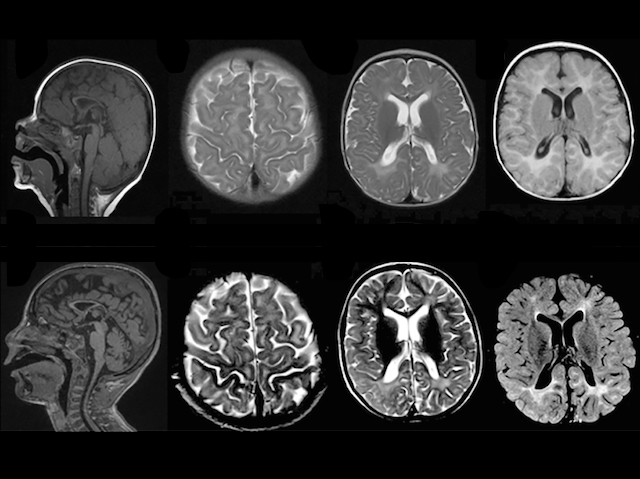

Baby B’s parents first realised something wasn’t right when he was just a few months old. His head seemed small and there were problems with his muscles and joints. By five, he still couldn’t walk, talk or see properly, and was prone to seizures. These MRI brain scans, taken at nine months (top row) and five years (bottom) reveal the problem: a condition known as genetic leukoencephalopathy (gLE). Normally the brain is made up of a mixture of grey matter (made of processing nerve cells) and white matter, formed of connecting and supporting cells. Children with this type of gLE have a fault in a gene called VPS11, leading to too much white matter in their brain. Sadly for B and his family there is currently no cure for the condition. But scientists hope that understanding what’s happening at a molecular level will uncover ways to help in the future.